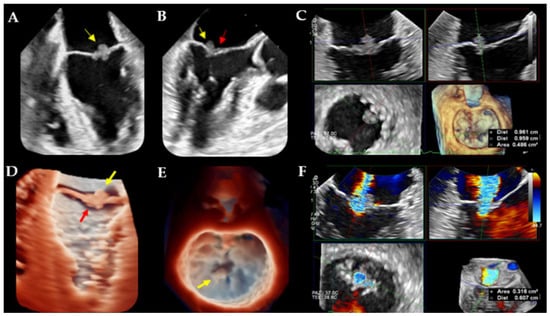

- The fundamental role of multimodality imaging (TTE + TEE, brain MRI, 18F-FDG/PET–CT scan) for NBTE diagnosis;

- The role of 2D and 3D-TEE for detection and characterization of NBTE valvular lesions;